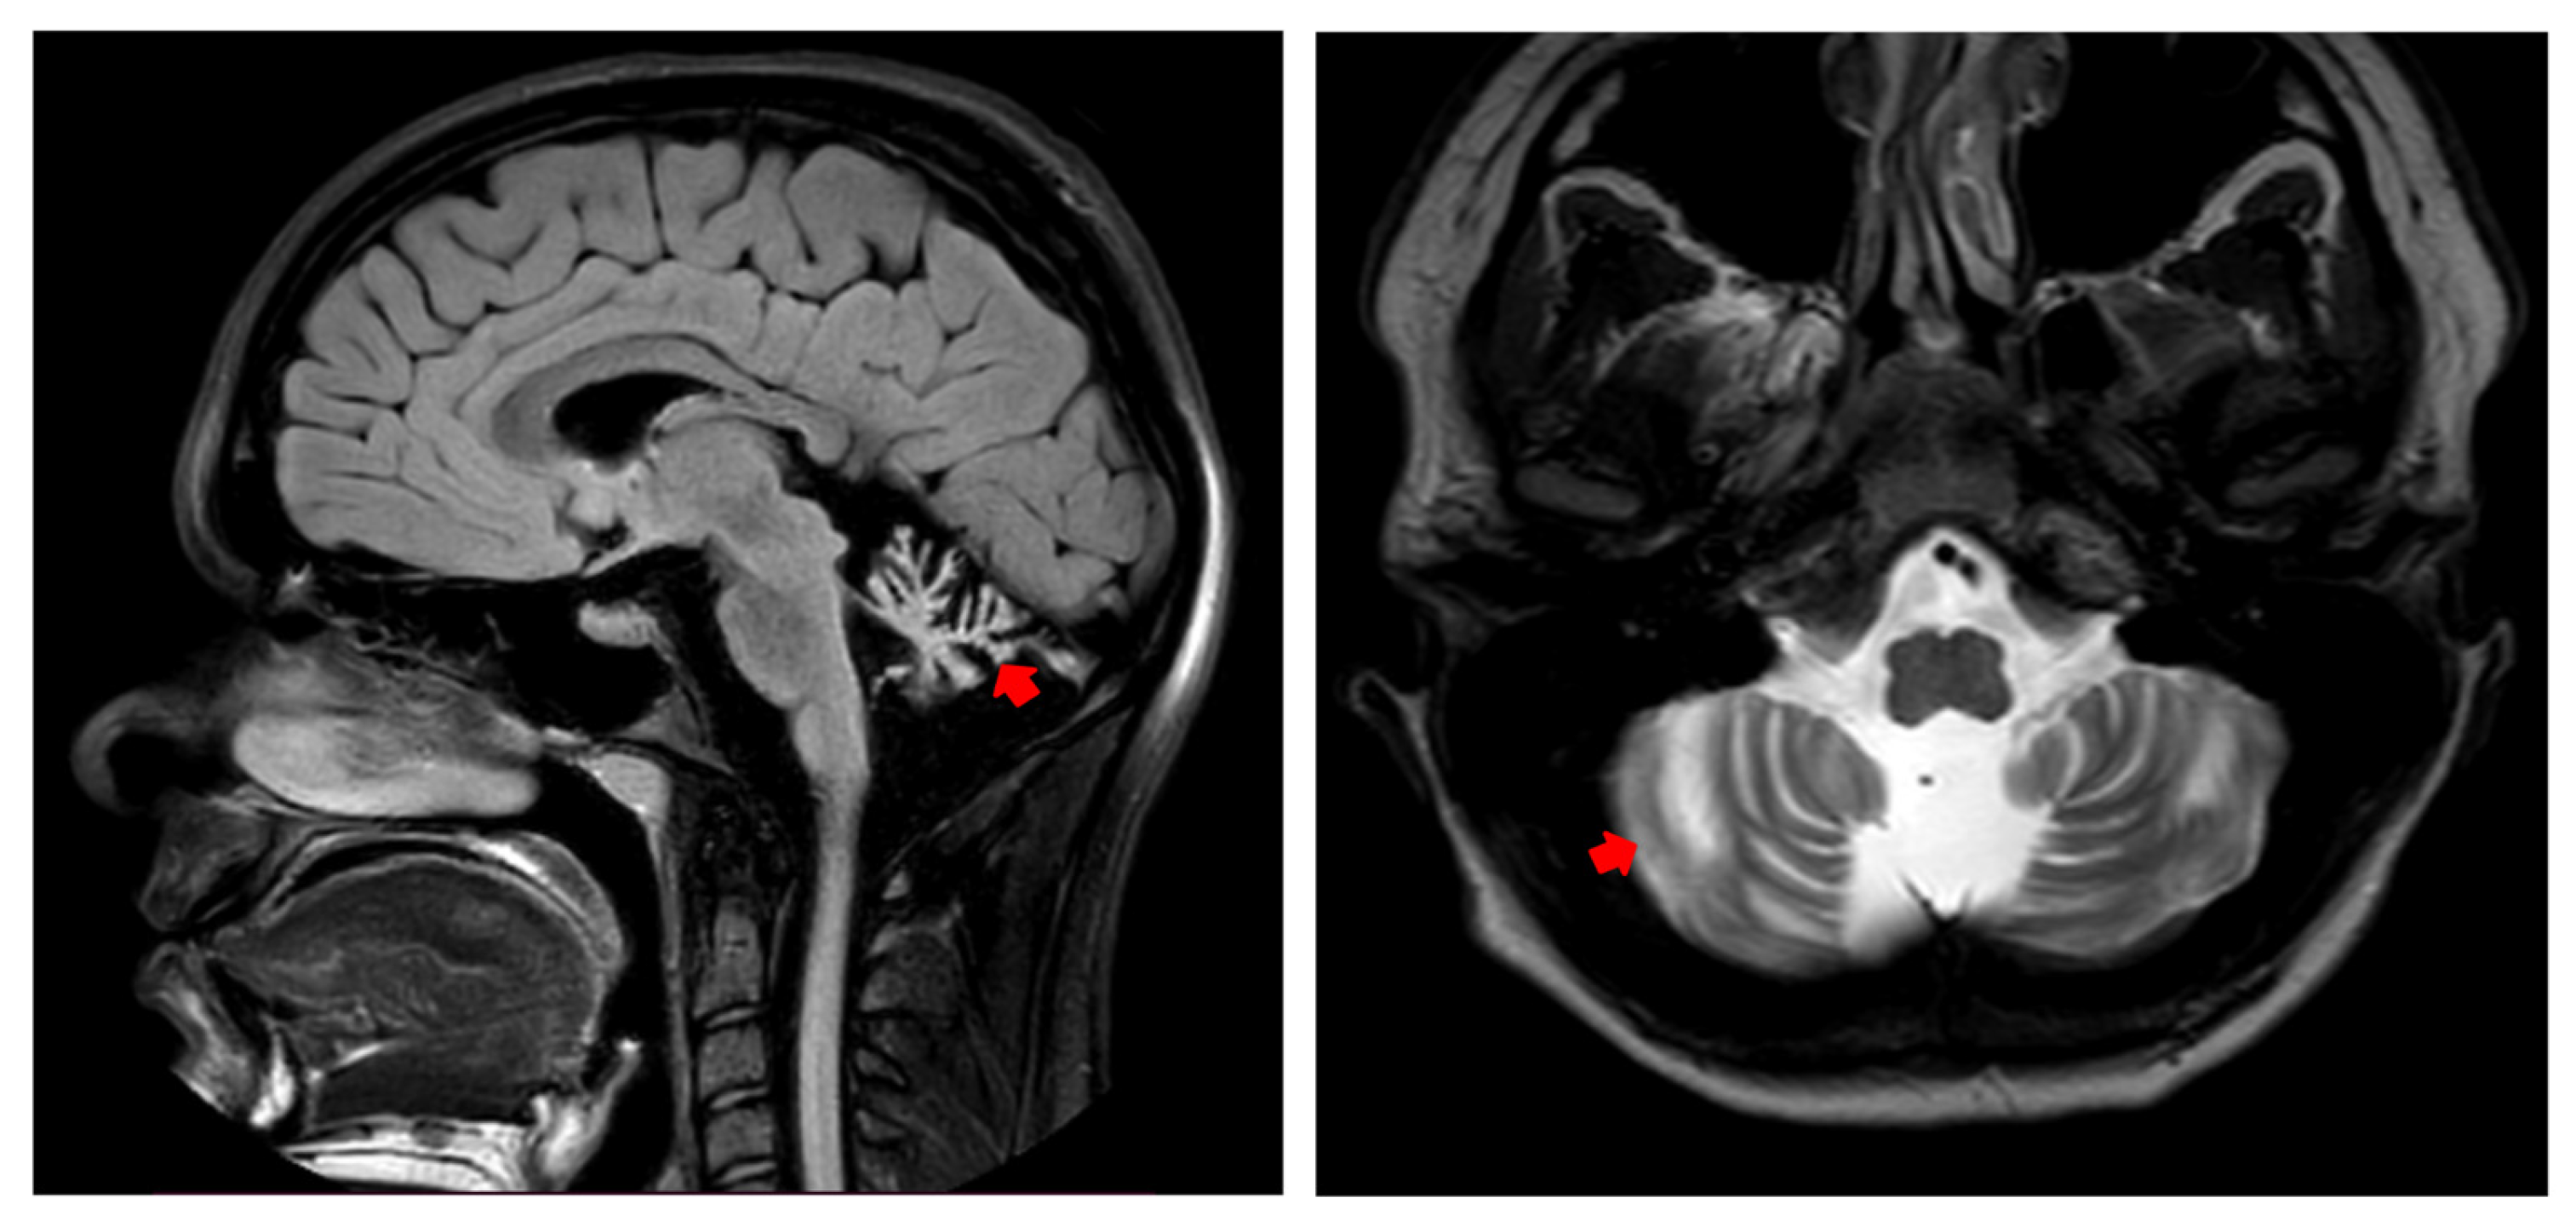

3.1. Clinical Case

3.2.3. Evaluation at 17 Years Old